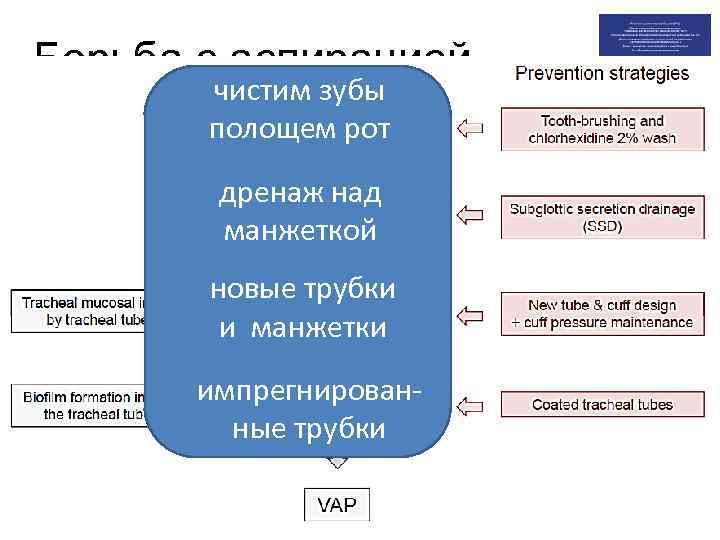

Борьба с аспирацией чистим зубы полощем рот «особенные» трубки дренаж над манжеткой новые трубки и манжетки импрегнированные трубки

Борьба с аспирацией чистим зубы полощем рот «особенные» трубки дренаж над манжеткой новые трубки и манжетки импрегнированные трубки